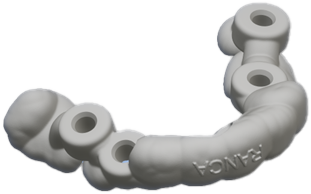

COMiP braces and invisible braces have the same origin. As for the Tooth positioner invented by Keslin in 1942, it was initially used as a maintainer after the correction, Because the Tooth positioner has the ability to position the corrected teeth, adjust the angle and obtain more occlusal contact, Therefore, it can help with tooth movement and correct minor dental differences. Subsequently, multiple sets were used to incrementally move teeth, and this feature was developed into Tooth positioner orthodontic.

The traditional tooth positioner is made in the same way as dentures. According to the upper and lower bite records, the upper and lower articulators are used to make braces that the upper and lower parts can bite together.

In the 1960s, vacuum thermoplastic materials appeared to make maintainers. This method was simpler and more convenient than the Tooth positioner used before. It did not require an articulator and was manufactured directly on the plaster model. The method of using vacuum thermoplastic materials to make retainers is still in use today.

In 1970, Ponitz developed early translucent correction based on the concept of Tooth positioner orthodontic at that time. Until Hermit Beauty uses digital design of teeth and 3D printing to produce invisible braces, Slight increments and multiple pieces allow for more space movement, fulfilling Keskin’s wish back then. However, this correction method lacks the interactive movement of the upper and lower bites. Therefore, it can effectively align the teeth, but it cannot accurately align the upper and lower bites.

The technology of the 21st century, the application of oral scanning and orthodontic software, has given the traditional Tooth positioner orthodontic a glimmer of hope. Nowadays, the teeth can be arranged neatly in the same way as invisible braces, and then based on the characteristics of the Tooth positioner, braces with gnathological positioner can be made based on the teeth arranged in a type of occlusal position.

The advantage of this designed Tooth positioner silicone braces is that, like invisible braces, the teeth are moved through the power of vertical occlusion, and the teeth can be arranged according to the ideal occlusal relationship.

COMiP uses the characteristics of Tooth positioner to establish the occlusion relationship of the Maximal Intercuspal Position (MIP) of Class I occlusion. This position is also called Central Occlusion (CO). During the mixed dentition period, it guides the tooth alignment of the upper and lower jaws. The method of positioning is used to guide the growth and arrange the teeth. Finally, the teeth are replaced and the teeth are arranged neatly.

COMiP two-stage early correction system. Our design has patents in many countries around the world. It is also the only system in the world that has four corrections. It is used in early correction. During the correction process, bone, teeth, muscle function and respiratory tract correction are gradually completed, providing a comprehensive solution. Problems with growing children. How to complete correction in two stages